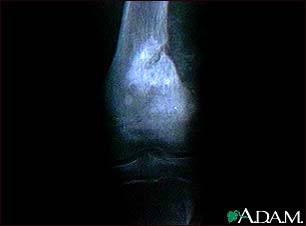

Osteogenic sarcoma - X-ray

This x-ray shows a malignant bone tumor (osteogenic sarcoma) of the knee. This type of tumor is usually seen in adolescents (around 15 years old). This tumor extends from the bone into the surrounding tissue.